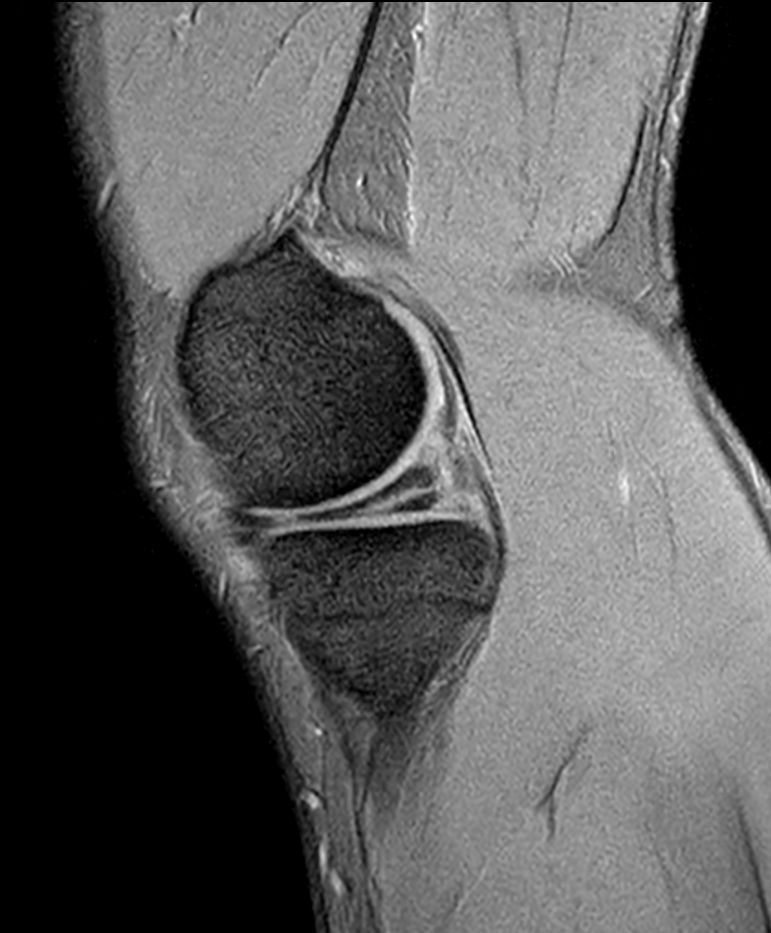

Knee with lesion

Patient with a Knee lesion. Compressed SENSE is used to shorten the total exam time.

PDw TSE - Compressed SENSE